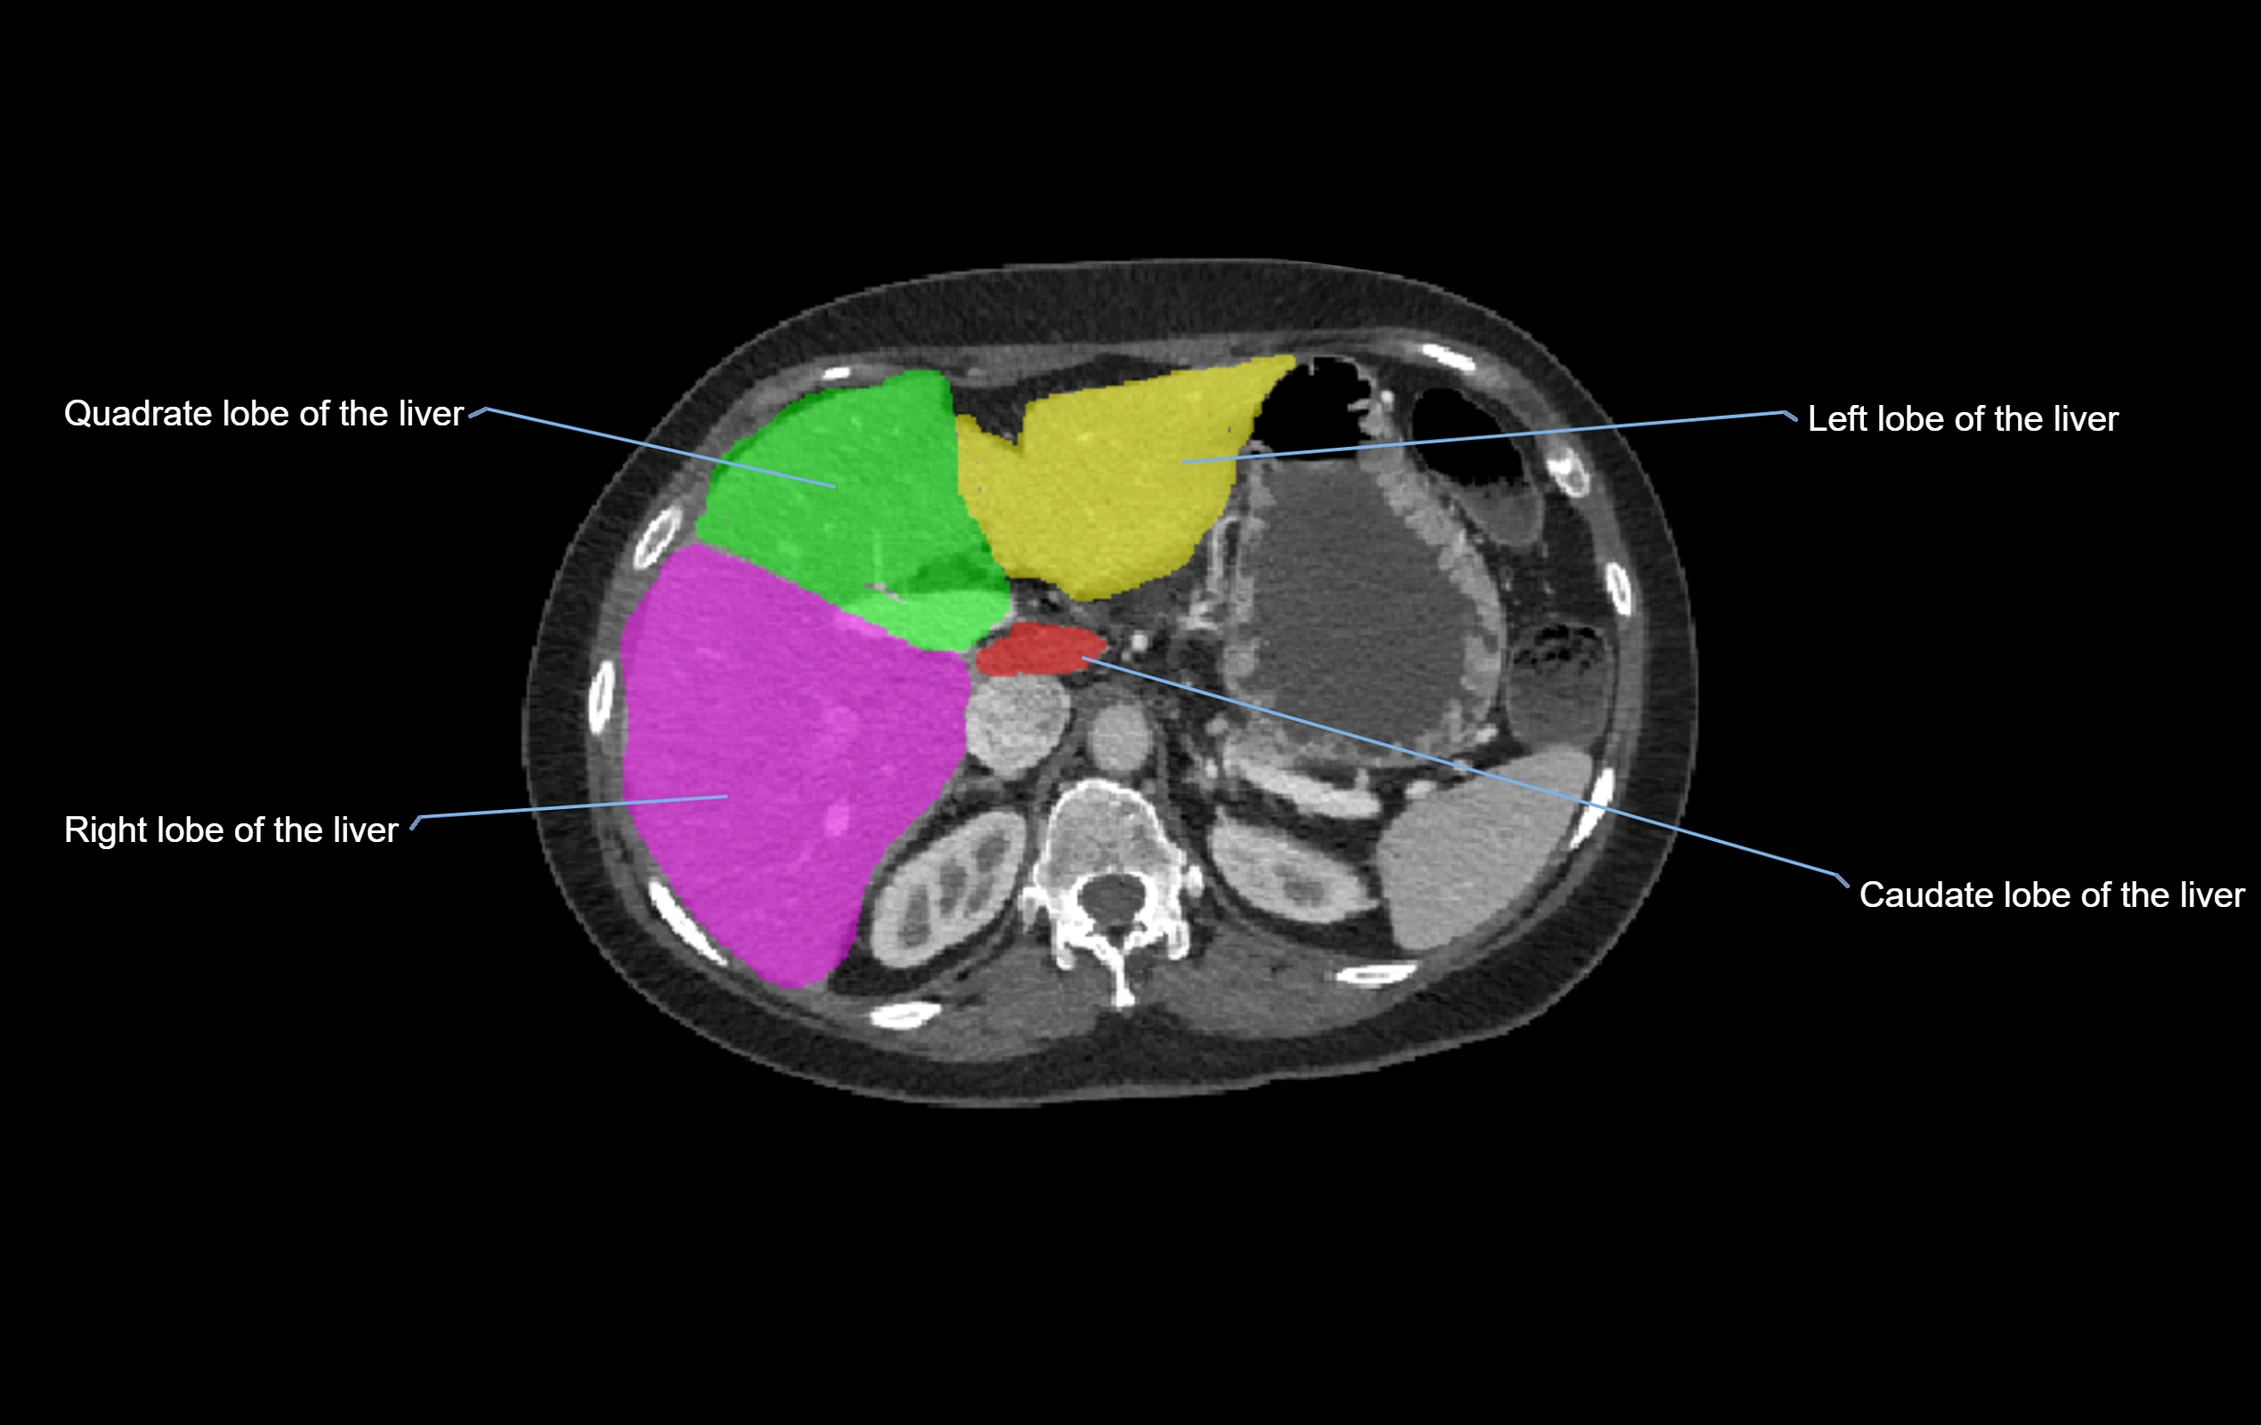

CT Image

image